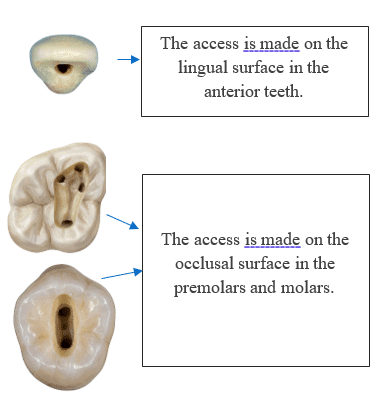

Anterior Teeth: Middle of the palatal side (preserve facial enamel).

Premolars: Middle of the occlusal.

Molars: Central fossa, slightly to the mesial.